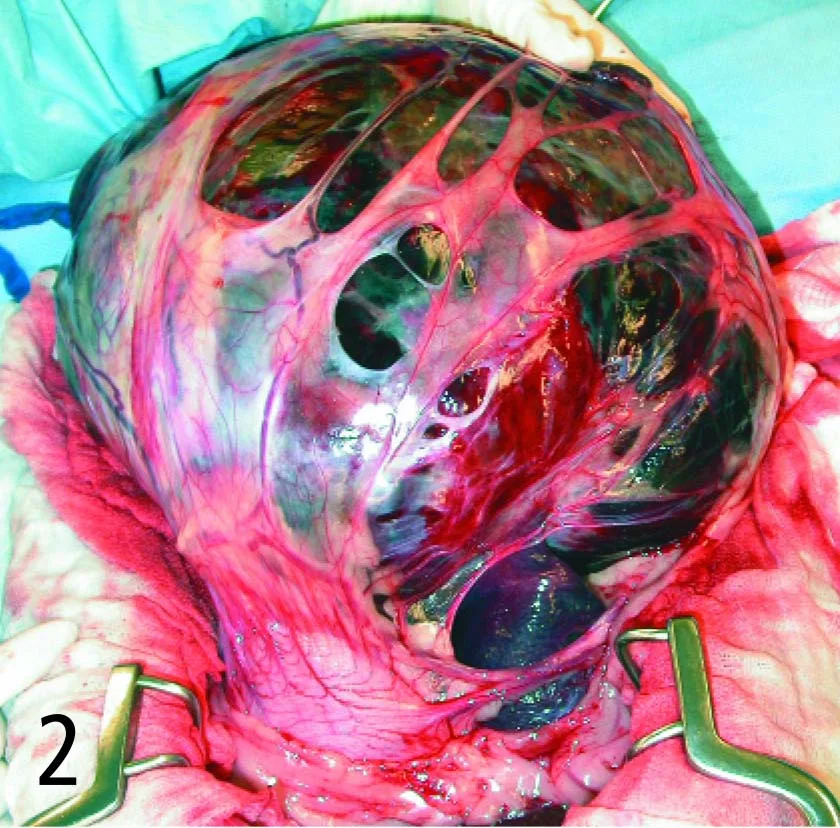

Omentum adhering to splenic masses can harbor a substantial number of vessels that require ligation (Figure 2). Ligate and remove these adhesions well away from the mass first before attempting pedicle ligation. It is acceptable to ligate any main splenic branches attached to, or encompassed within, the tumor to help ensure removal of all gross evidence of neoplasia, as long as adequate collateral gastric blood supply is available.